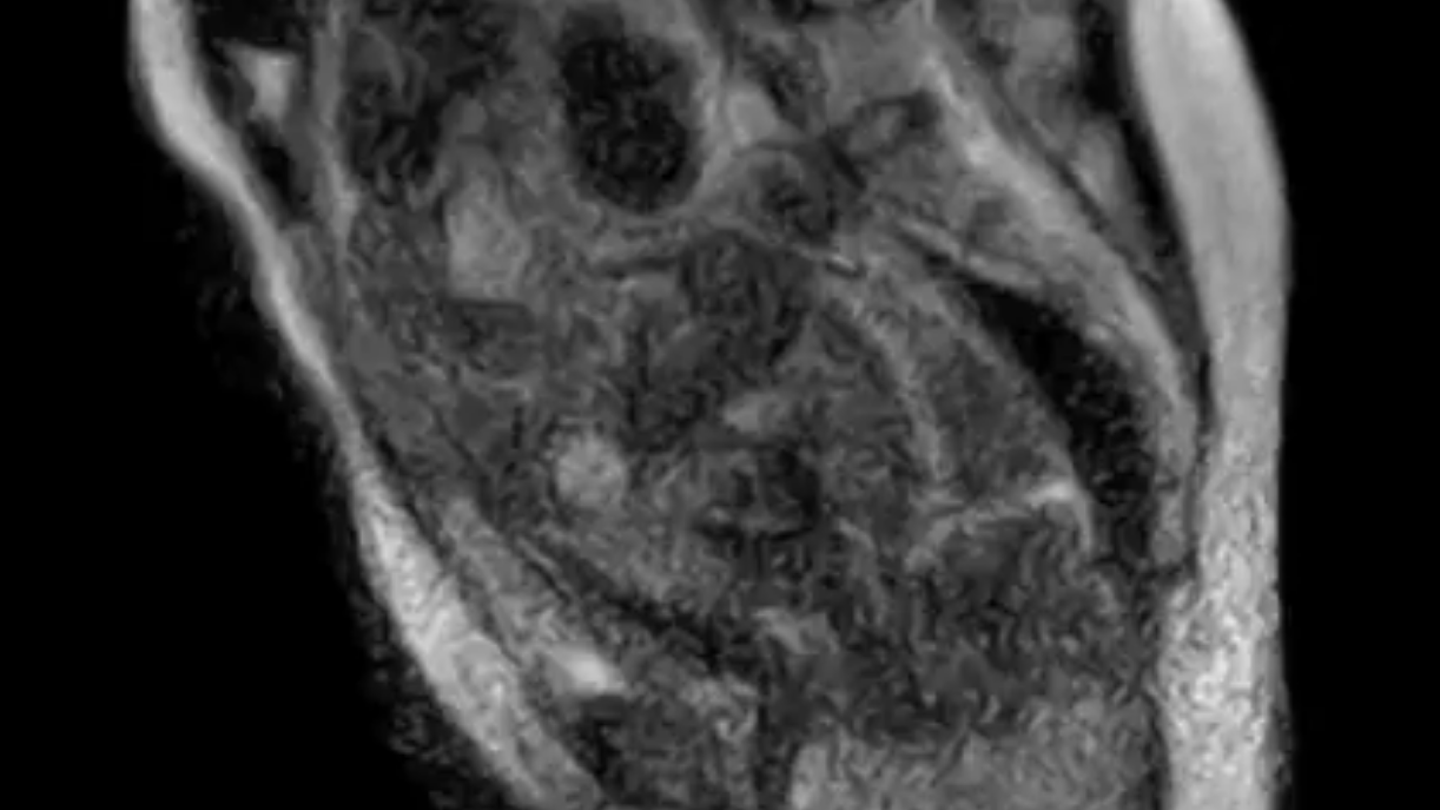

La fascination pour les IRM et les fonctions humaines ne cesse de croître. Ces images en coupe du cerveau et du corps permettent de visualiser de manière précise l’anatomie et le fonctionnement des organes internes. Les progrès technologiques dans le domaine de l’imagerie médicale ont considérablement amélioré la qualité des images et la précision des diagnostics.

Les IRM, ou Imagerie par Résonance Magnétique, utilisent un champ magnétique puissant et des ondes radio pour créer des images détaillées des tissus internes du corps. Contrairement aux rayons X ou aux scanners CT, les IRM n’utilisent pas de radiation ionisante, ce qui en fait une technique d’imagerie sûre et non-invasive.

L’IRM cérébrale est particulièrement utile pour étudier les maladies neurologiques telles que l’AVC, la maladie d’Alzheimer ou les tumeurs cérébrales. Les images en 3D permettent aux médecins de visualiser les différentes zones du cerveau et d’identifier toute anomalie ou lésion éventuelle.